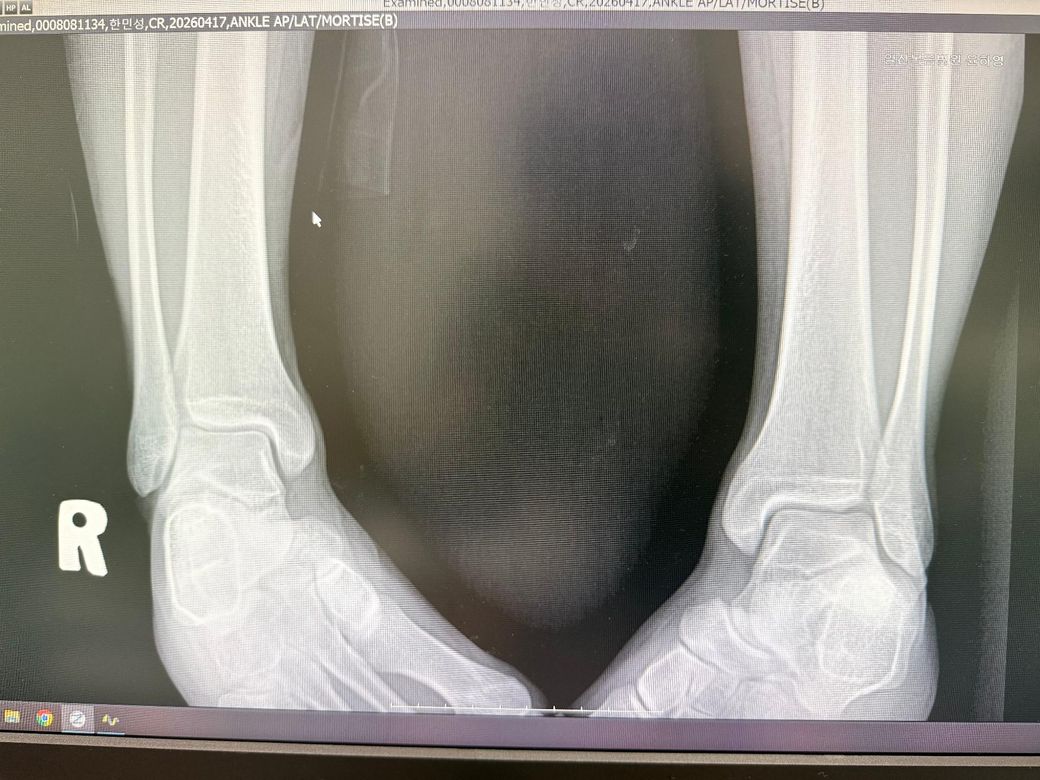

엑스레이 찍어보니 염좌 진단을 받았는데

• 1번 째 사진

• 2번 째 사진

• 3번 째 사진